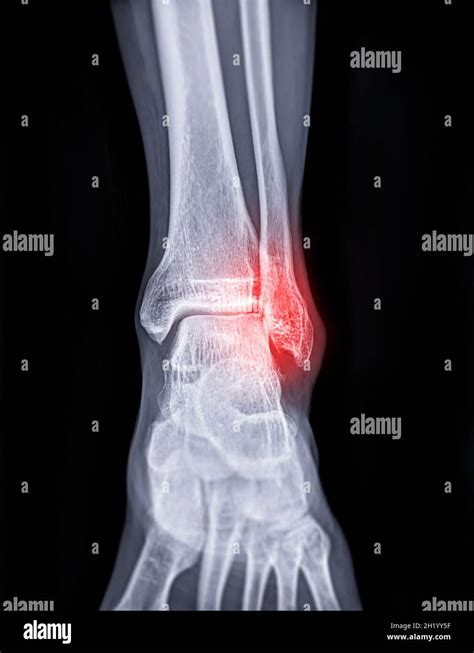

- Rayos X: Son la técnica más común y accesible. Permiten visualizar si el hueso está fracturado, si hay desplazamiento (separación entre los fragmentos óseos) y cuántos fragmentos existen. Se suelen tomar radiografías de la pierna, el tobillo y el pie para descartar otras lesiones.

- Prueba de Estrés: Dependiendo del tipo de fractura, el médico puede aplicar presión en el tobillo y tomar una radiografía especial. Esta prueba ayuda a determinar si ciertas fracturas requieren cirugía.